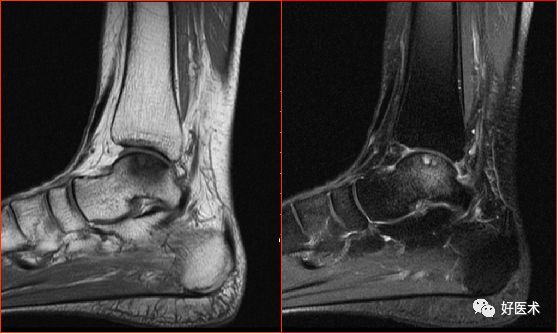

跟腱撕裂

胫骨后肌肌腱撕裂